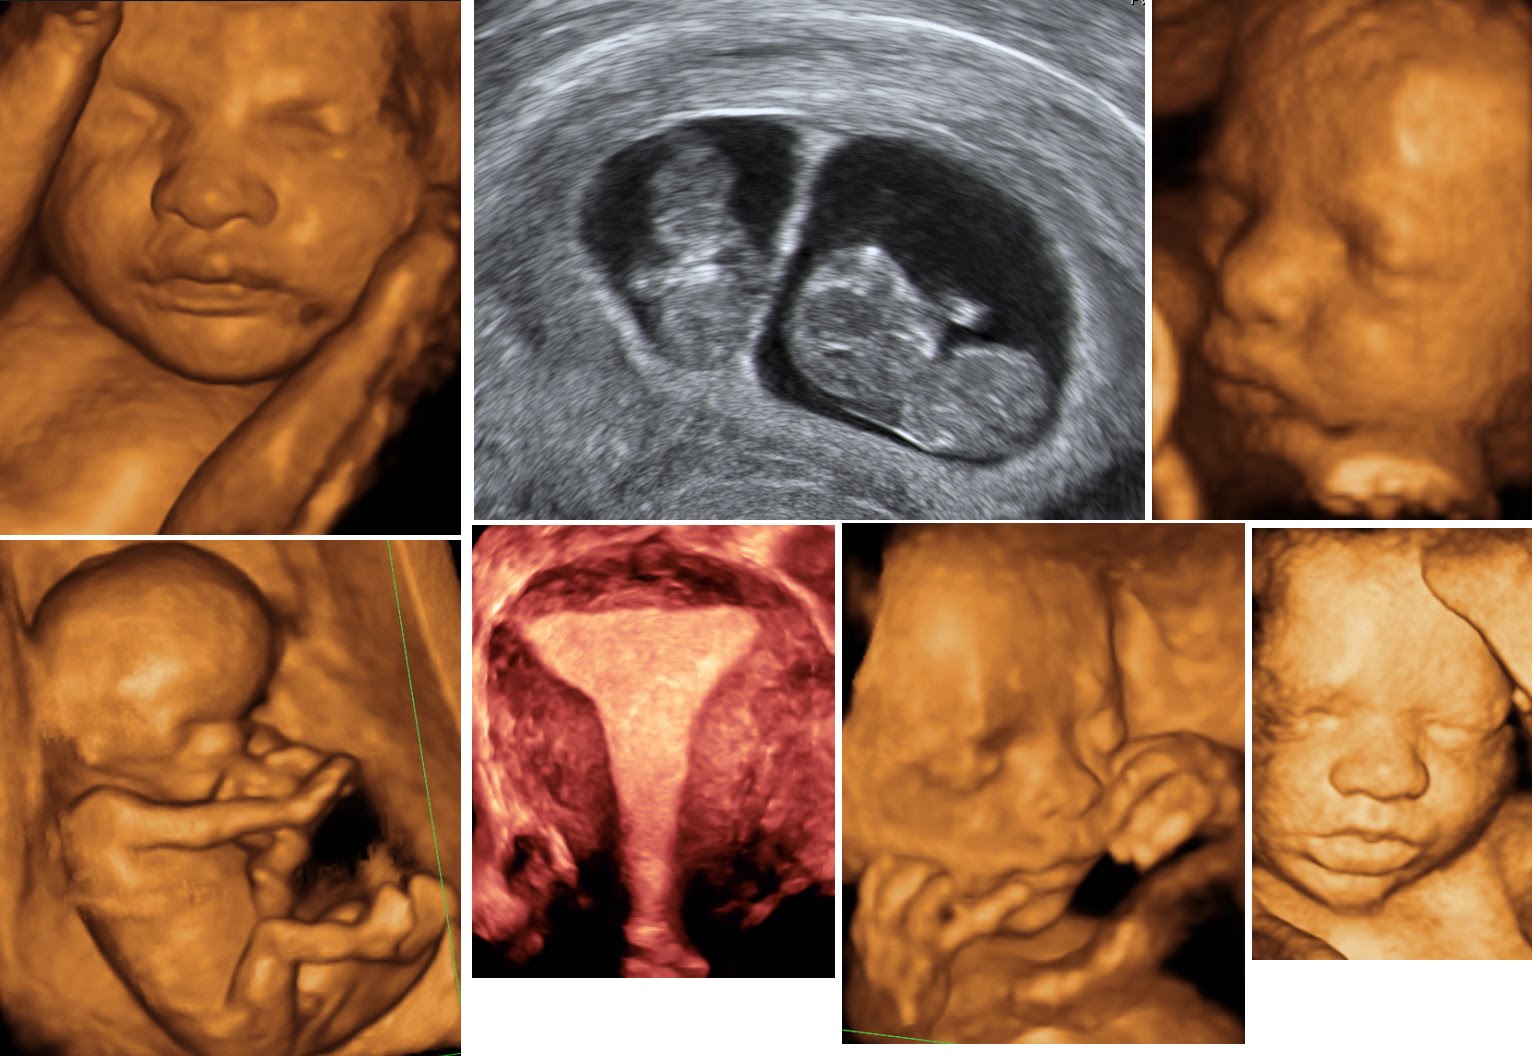

Bu nedenle ilk üç aylık dönem “altın dönem” kabul edilmektedir. Anne babalar, başka bakıcıları da sarsılmış bebek sendromunun tehlikeleri hakkında eğitebilirler. 1 cevap 000 görüntülenme cevaplar (1) uzm. Bu nedenle ilk üç aylık dönem “altın dönem” kabul edilmektedir. Röntgen ilk üç aylık dönem içerisinde çekilirse bebekte oluşum bozukluklarına neden olabilir. Bebek dişleri geçici olmasına rağmen, sağlıklı sabitlerin oluşması için tedavi edilmelidir. Mümkünse, çocuğu elin dijital röntgeni yapmak tavsiye edilir: Öte yandan anne karnında gelişimi devam etmekte olan bebek için zararlı olduğu kabul edilmektedir. 1 yıl satış sonrası servis:

Bebek dişleri geçici olmasına rağmen, sağlıklı sabitlerin oluşması için tedavi edilmelidir. Bu bebeklere kan, idrar tetkiki, kültür testi, akciğer röntgeni ve bel suyu (lomber ponksiyon) tetkikleri yapılabilir. Röntgen ilk üç aylık dönem içerisinde çekilirse bebekte oluşum bozukluklarına neden olabilir. Genellikle rahim röntgeni (hsg) sonuçları, işlem bittikten sonra 10 ila 20 dakika sonrasında çıkar. 1 yıl satış sonrası servis: Tele (kalp röntgeni) kalp röntgeni (telekardiyogram = tele):

Öte yandan anne karnında gelişimi devam etmekte olan bebek için zararlı olduğu kabul edilmektedir. Gelişen teknoloji, döner aletler ve apex locator adı veriken kök ucu bulucu cihaz sayesinde, röntgen çekmeye gerek kalmadan gebelikte kanal tedavisi yapılabilir. Bir çocuğa zarar verebilecek anne babalar için yardım mevcuttur. Diş röntgeni çektirilirken cihazın yaydığı x ışınları, direk karnın alt kısmını hedef almamaktadır. Terapi arifesinde, süt dişleriyle çenenin röntgeni yapılır. Biri çocuk röntgeni mi dedi🙃🙆🏻♀️ #iyigeceler.

1 yıl satış sonrası servis: Mrb doktor bey ,benim şu anda 9 aylık bir kızım var,kalça için 4 aylıktan itibaren 7 tane kalça röntgeni çekildi,sol tarafta açı geniş çıkıyormuş 4 farklı doktor gördü ancak hiç birisi kesin birşey söylemedi en son. Bu sonuçlar, diğer röntgen filmlerinde olduğu gibi siyah röntgen kağıtlarına basılmaktadır. Hamilelik döneminde bebeğin ilk üç ayı çok önemlidir. Röntgen sayesinde akciğer daha net görüntülenerek teşhisin daha kolay. Bu sayede problem olduğunda şeklinin uygun tedaviyle düzeltilmesi ve vücudun buna uyumu, yeniden şekillenmesi çok daha hızlı ve tam olmaktadır.

Bu nedenle ilk üç aylık dönem “altın dönem” kabul edilmektedir. #uluslararasicocuksagligi #çocuk #sağlık #anne #bebek #children #hospital #health #baby #xray. Hamilelikte kanal tedavisi başta olmak üzere diş tedavilerinin yapılıp yapılamayacağı birçok anne adayı için merak konusudur.peki, hamilelikte kanal tedavisi yapılabilir mi?

Genellikle rahim röntgeni (hsg) sonuçları, işlem bittikten sonra 10 ila 20 dakika sonrasında çıkar. Bebek için daha güvenli ve daha rahattır. Akciğer filmi iki yönlü olarak çekilir, akciğerler önden ve yandan çekilerek çevre organlarda ve göğüs boşluğunda oluşabilecek hastalıklara da tanı.

Tüm hastanelerde röntgen odasına hamileler giremez ibaresi koyulmaktadır. 1 yıl satış sonrası servis: Hafta arasında yapılan tek seferlik röntgenler bebekler için herhangi bir sorun yaratmamaktadır.

AYRINTILI DETAYLI ULTRASON DOPPLER RENKLİ DOPPLER FULL

Bebekler herhangi bir dokunun röntgeni çekilmesi ile alakalı yapılan araştırmalar neticesinde bebeklerin yaklaşık olarak % 12’lik kısmında, 3 yaşına kadar 4 tane bebekten 1 tanesinde 2’den defa fazla, her 7 çocuktan 1 tanesinde 3 ya da daha çok röntgen çekimi yapılmış olması uzmanları da endişelendirmektedir. Röntgen sayesinde akciğer daha net görüntülenerek teşhisin daha kolay. Sağlıklı bir hamilelik için gereksiz ilaç kullanımından uzak durmalı ve doktor önerisi olmadan hiçbir tedaviye başlamamalısınız.

A post shared by (@uluslararasicocuksagligi) on oct 4, 2019 at 11:56am pdt Hamilelik döneminde çekilen röntgen filmlerinden dolayı bebeğin maruz kaldığı radyasyon miktarları genellikle çok düşüktür. Bu durum bebek açısından son derece sakıncalıdır.eğer çok ciddi bir durum söz konusu ise hamileliğin ikinci üç aylık evresinde koruyucu yeleklerle.

A post shared by (@uluslararasicocuksagligi) on oct 4, 2019 at 11:56am pdt Hastane radyoloji ekipmanı röntgen tıbbi dijital panoramik diş röntgeni makinesi $ 60,000.00 Bebeklerde ilk üç ayda kalça eklemini oluşturan yapılar kıkırdaktır.